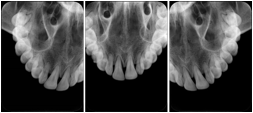

2. A patient requests cosmetic surgery to enhance their facial appearance. The case requires consultation between an orthodontist in New York and an oral surgeon in California. The cephalometric series of 2D projections constructed from the volumetric CT data that is used for the discussion is arranged by a Structured Display for transfer between the two practitioners.

Cephalometric Series Structured Display

Figure OO-2. Cephalometric Series Structured Display